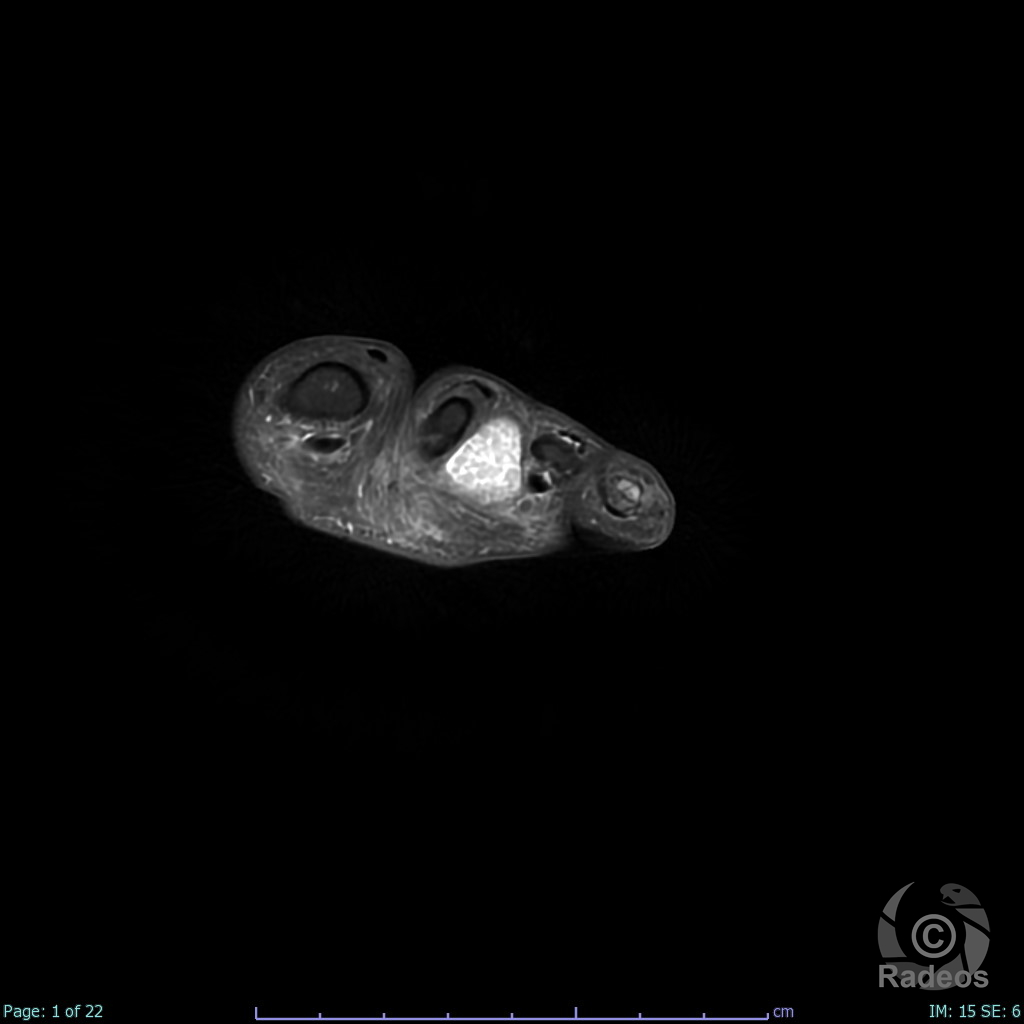

Aspect IRM d'une fibromatose profonde de la paroi abdominale. Découverte fortuite d'un angiome hépatique gauche.

Fibromatose profonde de type desmoïde